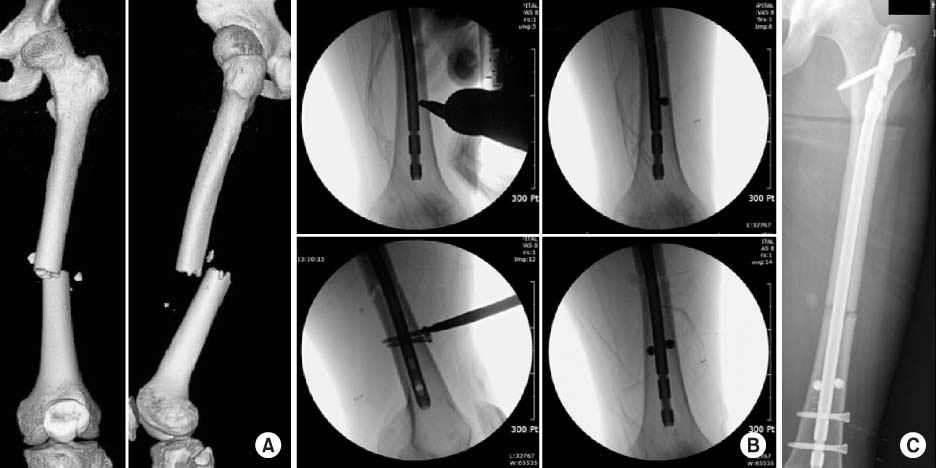

Fig. 3

(A) Three-dimensional-reconstructed computed tomography images at postoperative 5 months show full consolidation of a complex femur shaft fracture including neck fracture component. (B) However standing lower extremity scanogram shows a limb length discrepancy of 15 mm.

Fig. 3 (A) Three-dimensional-reconstructed computed tomography images at postoperative 5 months show full consolidation of a complex femur shaft fracture including neck fracture component. (B) However standing lower extremity scanogram shows a limb length discrepancy of 15 mm.